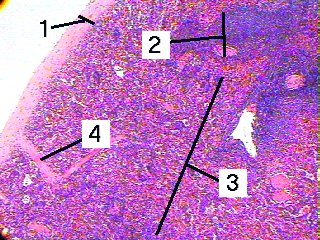

Fig 64-001

A low magnification of the spleen demonstrating the capsule and white and red pulps.

1. Capsule

2. White pulp

3. Red pulp

4. Trabecula